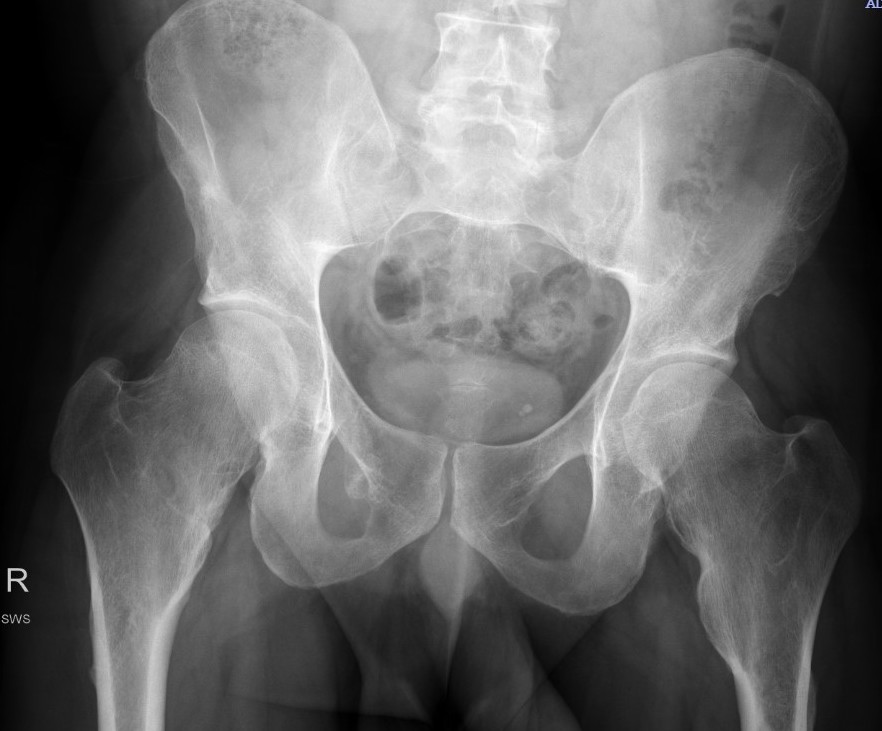

Hip

- coxa valga

- neck short & broad

Mult OC hipHip Osteochondroma

Hip HME

Issues

Coxa valga

Hip subluxation